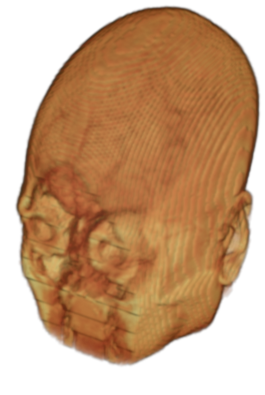

The digitalization of heath records has increased the risk of –and impact of– large scale data leaks. Although data compliance standards have been enacted to protect health records (HIPAA and GDPR), privacy of medical data is a growing concern. Three-dimensional scans such as magnetic resonance images (MRI) and computed tomography (CT), for example, contain an intrinsic privacy risk [Lotan et al.(2020)Lotan, Tschider, Sodickson, Caplan, Bruno, Zhang, and Lui]. Detailed renderings of the head can be crafted from 3D scans using techniques such as volumetric raycasting, as in Figure 1. This vulnerability can expose the patient’s identity if the renderings are matched to a face database [Mazura et al.(2012)Mazura, Juluru, Chen, Morgan, John, and Siegel, Lotan et al.(2020)Lotan, Tschider, Sodickson, Caplan, Bruno, Zhang, and Lui].

To prevent these types of attack, medical scans are currently de-identified using crude removal-based techniques [Bischoff-Grethe et al.(2007)Bischoff-Grethe, Ozyurt, Busa, Quinn, Fennema-Notestine, Clark, Morris, Bondi, Jernigan, Dale, Brown, and Fischl, Schimke et al.(2011)Schimke, Kuehler, and Hale, Milchenko and Marcus(2013)] which seek to remove privacy-sensitive parts of the head (examples in Figure 3). However, as we demonstrate, these existing techniques fail to reliably hide the patient’s identity – or they are so aggressive that they impair further medical analyses. A better solution is needed.

Benchmark De-Identification Methods. We compare our result with three publicly available and widely-established methods for de-identification of MRI head scans, depicted in Figure 3. All methods have in common that they (1) are not deep-learning-driven, (2) require no additional training and (3), are used on a day-to-day basis in neuroscience and clinical research. All procedures were applied with default settings on images of resolution . The methods include QUICKSHEAR [Schimke et al.(2011)Schimke, Kuehler, and Hale], FACE MASK [Milchenko and Marcus(2013)], and DEFACE [Bischoff-Grethe et al.(2007)Bischoff-Grethe, Ozyurt, Busa, Quinn, Fennema-Notestine, Clark, Morris, Bondi, Jernigan, Dale, Brown, and Fischl]. Descriptions of the methods are provided in the Appendix. We also include MRI WATERSHED [Ségonne et al.(2004)Ségonne, Dale, Busa, Glessner, Salat, Hahn, and Fischl], a skull-stripping method that removes everything except the brain.